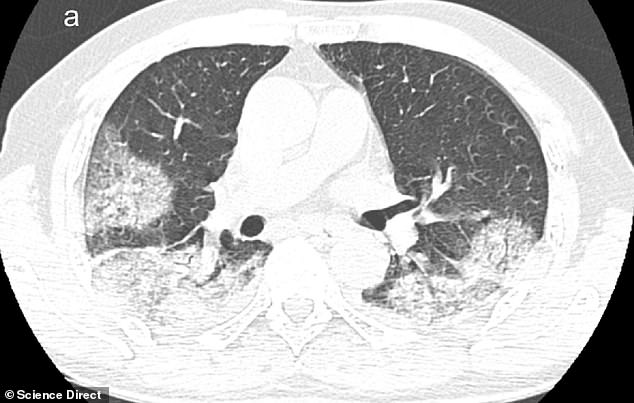

Το ίδιο συμβαίνει και στη μαγνητική τομογραφία στους πνεύμονες όπου στη μια είναι καθαροί και στην άλλη έχουν γεμίσει πυον, νερό ή αίμα.